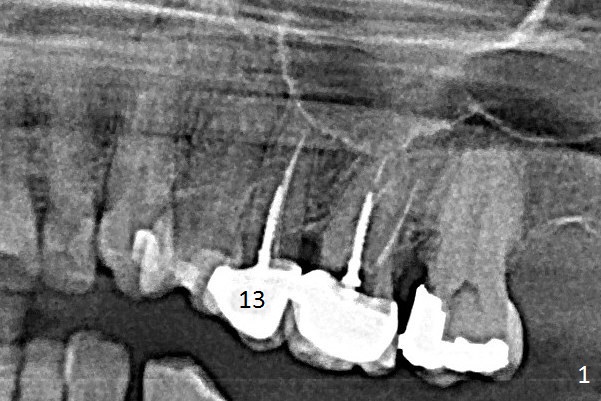

A 60-year-old woman returns to office with chief complaint "upper left crown is loose again".  Clinical exam confirms #13 crown fracture at the gingival level (Fig.1,2 *).  Since the native bone is short, an implant (Fig.3 green) should penetrate the sinus floor for primary stability.  To protect the sinus membrane, PRF membranes (purple curved line) will be inserted prior to bone graft (red circles) and the implant.  A pair abutment is expected to be 5x5 (5.7 exactly, blue) (Fig.3, pink) mm.  The implant should be placed palatally to avoid buccal metal show through.